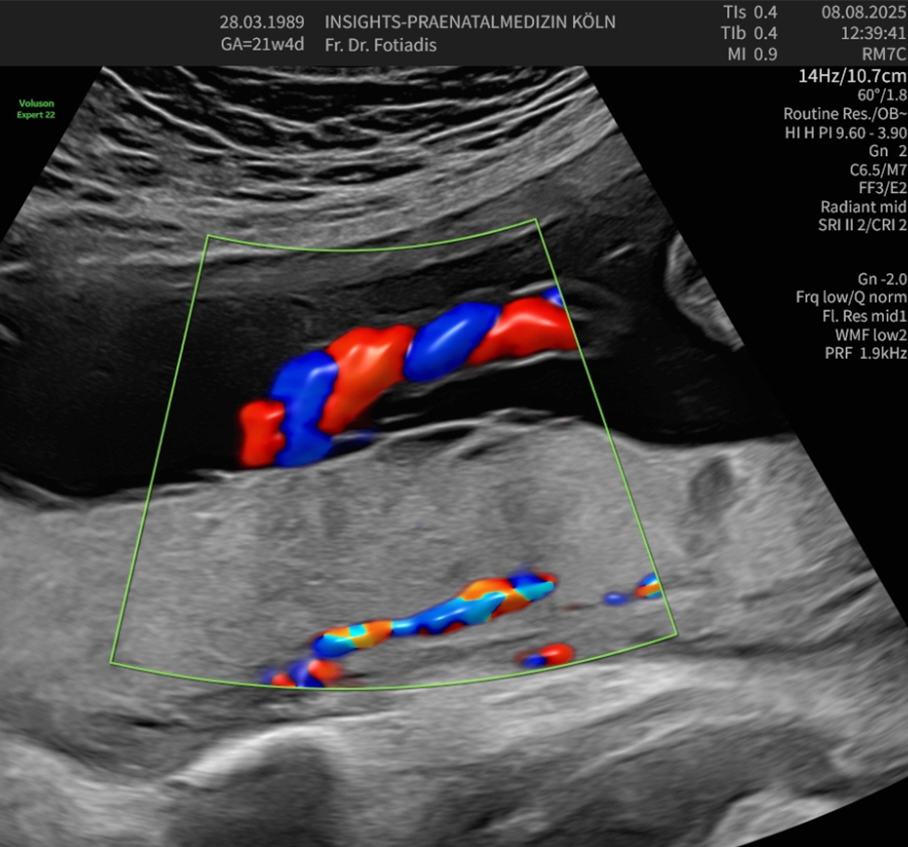

Diese spezielle Untersuchungsmethode dient der Überprüfung von Blutflüssen und Flussgeschwindigkeiten in der Gebärmutter und in verschiedenen kindlichen Blutgefäßen. Mittels Dopplersonographie sind wir in der Lage, die Blutversorgung wie auch die Herzfunktion und Kreislaufsituation des Kindes zu beurteilen. Ebenso kann eine fetale Anämie (Blutarmut) erkannt werden.

Die Beurteilung der mütterlichen Gebärmutterarterien erlaubt eine Abschätzung des Risikos für das Auftreten einer Schwangerschaftsvergiftung (Präeklampsie) oder einer Wachstumsstörung des Kindes. Auf diese Weise können wir die Versorgungslage und in gewissem Maße auch das kindliche Befinden überprüfen, Mangelversorgungen aufdecken und die entsprechenden Maßnahmen bis hin zur vorzeitigen Entbindung treffen.